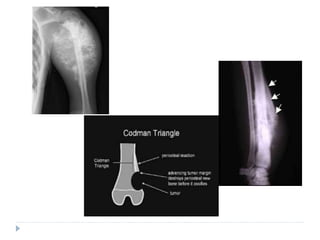

RADIOGRAPHIC FEATURES

 Three classic features are seen

 SUNRAY OR SUNBURST APPEARANCE: Small streaks

of bone radiate outward

 Due to osteophytic bone production on the surface of the lesion

 Appreciated best on occlusal radiographs

 Tumour may grow within the PDL space causing

resorption of the adjacent bone: resulting in uniform

widening of the PDL space

 This is an early radiographic change

 CODMAN’S TRIANGLE: In long bones affected with

osteosarcoma the periosteum is elevated over the

expanding tumour mass in a tent-like fashion

 At the point where periosteum begins to merge, an acute angle

is formed between the bone surface and the periostium

 This feature is highly suspicious of osteosarcoma